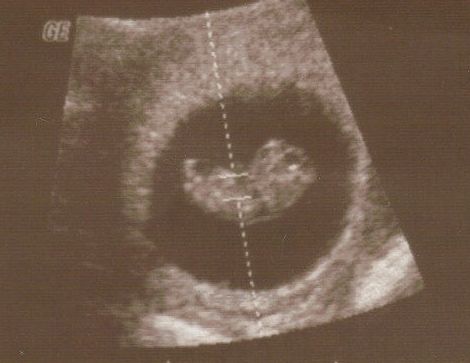

E-lona krótkie to u mnie w ramach każdej wizyty, tak ok 5 min, szybkie pomiary do szacunku wagi i kontrola przepływów. Dostaje tylko potem wydruk z pomiarami. A długie to te 3 zalecane: prenatalne, połówkowe i w okolicy 32tc i te u mnie trwają 30-40 min i wtedy dostaje duzo zdjęć i filmik

Teraz bede miała wizyte w 30 tc wiec nie wiem czy zechce już robic to długie czy zrobi tylko takie na szybko i umówimy sie na konkretniejsze końcem sierpnia.

zdecydowalam sie na to badanie bo chodze do gina na kase chorych wiec nie wszystkie badania mam dokladnie porobione... nawet nie znam wagi dzidziusia:-( i do tej pory nie chciało wcale pokazac co ma pomiedzy nozkami (wstydnis

). Mam nadzieje ze na 4d rozłoży ładnie nozki i pochwali sie czym je Bozia obdarzyła